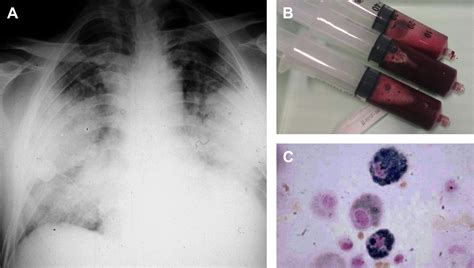

• Imaging Tests: Chest X-rays and CT scans can help visualize the lungs and identify areas of bleeding.

• Bronchoscopy: This procedure involves inserting a thin tube with a camera into the lungs to directly visualize the bleeding.

• Sputum Analysis: Examining the sputum (mucus coughed up from the lungs) can help identify the presence of blood and any underlying infections.

• diffuse alveolar hemorrhage bronchoscopy

• diffuse alveolar hemorrhage radiology

• diffuse alveolar hemorrhage cxr